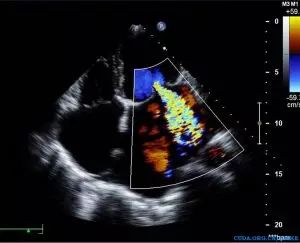

08

MitraClip治疗二尖瓣反流